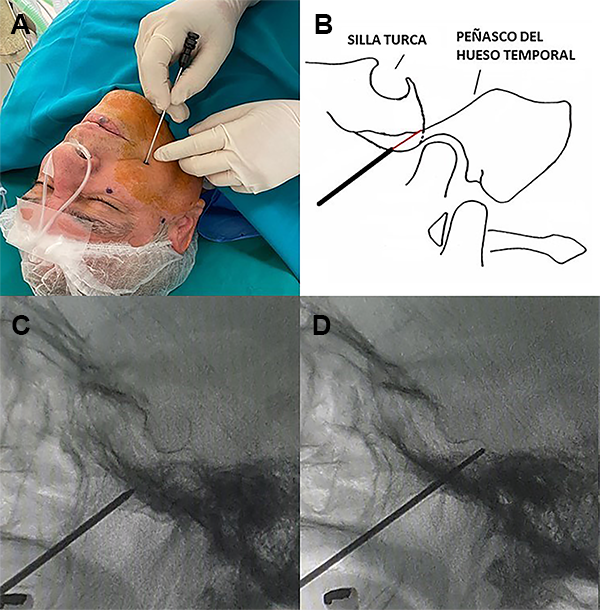

Se marcaron tres puntos referenciales en la hemicara comprometida: el primero a 2.5 cm lateral a la comisura labial, el segundo a nivel de la línea media pupilar y el tercero a 3 cm por delante del trago (Figura 3). Se realizó la limpieza y asepsia de la hemicara comprometida en torno al primer punto referencial con yodopovidona espuma y con yodopovidona solución. Se colocó el equipo de fluoroscopio arco en C para tener incidencia lateral del cráneo.

Figura 3: Puntos referenciales para acceder al agujero oval.

La punción del foramen oval se realizó siguiendo la técnica de Hartel;8 sin embargo, nosotros hacemos punción directa sin necesidad de insertar el dedo índice enguantado en la boca del paciente a lo largo del costado de los molares sobre el pterigoideo lateral. Esta maniobra ayudaría a guiar la cánula hacia el agujero oval y evitar la penetración de la mucosa. No realizamos incisión ni utilizamos anestesia local en el punto de entrada.

A través del primer punto de referencia en la hemicara comprometida, se introdujo una aguja metálica número 14 Gauge de 100 mm de longitud con mandril de 120 mm de longitud (Macom® São Paulo, Brasil).

La aguja guiada de los tres puntos referenciales en la hemicara y bajo control fluoroscópico debe dirigirse a un punto en la línea clival 5-10 mm por debajo del piso de la silla turca o en la intersección del peñasco del hueso temporal con el clivus, hasta que se engancha en el agujero oval. Es innecesario penetrar más allá del agujero. La aguja simplemente permanece en el agujero oval (Figura 5).

Figura 5: (A) Punto de ingreso de la aguja 14 G. (B) Esquema gráfico de la ubicación de la aguja y mandril. (C) Ingreso de la aguja al agujero oval, (D) Colocación del punzón guía para facilitar entrada de catéter Fogarty.